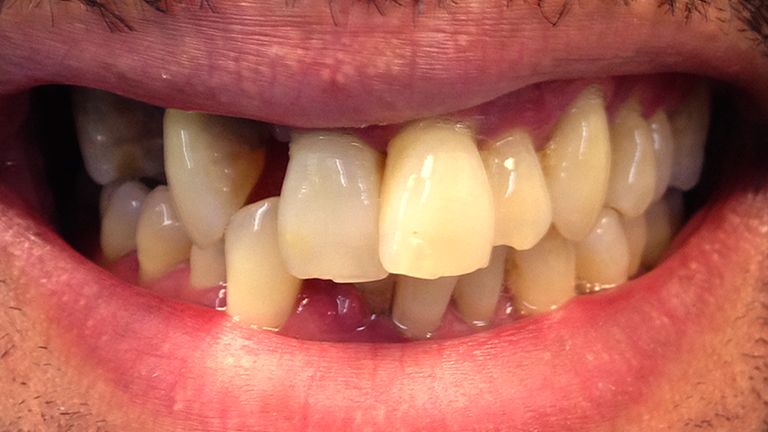

Below is a few examples of what DENTAL IMPLANTS can do for you and your smile!